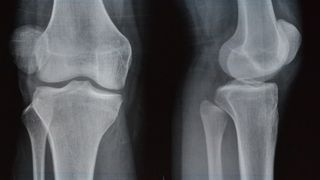

Acuzi de multa vreme dureri de genunchi sacaitoare si enervante? Trateaza-le cu seriozitate! Specialistii au descoperit ca o treime din populatia adulta experimenteaza un anumit tip de durere articulara in fiecare luna. Acestia sustin ca genunchii se afla printre zonele in care apar cele mai dese dureri. Iata insa cand trebuie sa te ingrijoreze o durere de genunchi si cand ar fi indicat sa te adresezi de urgenta medicului.

Durere de genunchi- Sindromul durerii patelofemorale

Sindromul durerii patelofemorale, cunoscut şi ca genunchiul alergatorului, este intalnit des in randul sportivilor amatori sau de performanta. Simptomele acestui sindrom pot include durere in spatele sau in jurul piciorului, durere in timp ce se indoaie piciorul, umflarea genunchilor sau senzatii de pocnituri si ,,macinare’’ in genunchi.

Sindromul durerii patelofemorale poate afecta unul sau ambii genunchi si in aceste cazuri este indicat sa mergeti la medic.

Durere de genunchi- Condromalacia rotuliana

Condromalacia rotuliana se refera la inmuierea si distrugerea cartilajului de pe partea inferioara a genunchiului sau a patelei. Este una dintre cauzele comune ale durerii genunchiului, mai ales la femei.

Condromalacia rotuliana este cauzata de o aliniere necorespunzatoare sau de pozitionarea necorespunzatoare a patelei in timp ce aceasta se deplaseaza peste femur. Cel mai frecvent simptom este o durere surda in spatele rotulei.